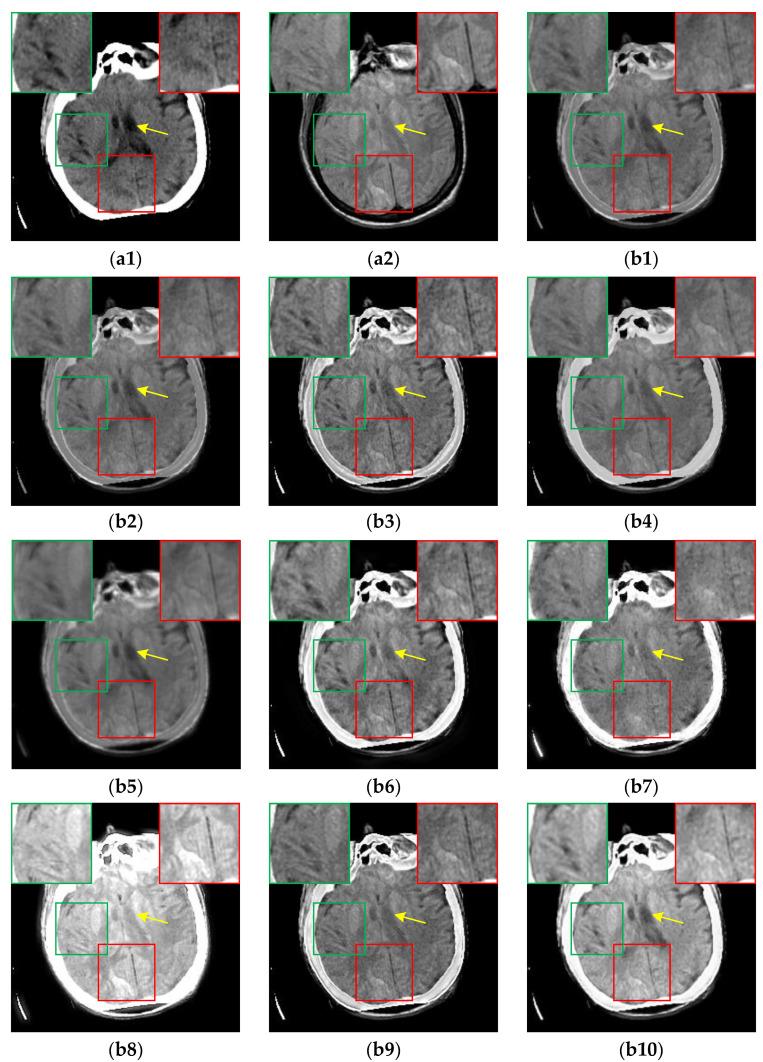

Multi-modal medical image fusion (MMIF) is crucial for disease diagnosis and treatment because the images reconstructed from signals collected by different sensors can provide complementary information. In recent years, deep learning (DL) based methods have been widely used in MMIF. However, these methods often adopt a serial fusion strategy without feature decomposition, causing error accumulation and confusion of characteristics across different scales. To address these issues, we have proposed the Coupled Image Reconstruction and Fusion (CIRF) strategy. Our method parallels the image fusion and reconstruction branches which are linked by a common encoder. Firstly, CIRF uses the lightweight encoder to extract base and detail features, respectively, through the Vision Transformer (ViT) and the Convolutional Neural Network (CNN) branches, where the two branches interact to supplement information. Then, two types of features are fused separately via different blocks and finally decoded into fusion results. In the loss function, both the supervised loss from the reconstruction branch and the unsupervised loss from the fusion branch are included. As a whole, CIRF increases its expressivity by adding multi-task learning and feature decomposition. Additionally, we have also explored the impact of image masking on the network's feature extraction ability and validated the generalization capability of the model. Through experiments on three datasets, it has been demonstrated both subjectively and objectively, that the images fused by CIRF exhibit appropriate brightness and smooth edge transition with more competitive evaluation metrics than those fused by several other traditional and DL-based methods.

多模态医学图像融合(MMIF)对于疾病诊断和治疗至关重要,因为从不同传感器收集的信号重建的图像可以提供互补信息。近年来,基于深度学习(DL)的方法已广泛应用于MMIF。然而,这些方法通常采用无特征分解的串行融合策略,导致误差累积和不同尺度特征的混淆。为了解决这些问题,我们提出了耦合图像重建与融合(CIRF)策略。我们的方法将图像融合和重建分支并行,通过一个公共编码器连接。首先,CIRF使用轻量级编码器分别通过视觉Transformer(ViT)和卷积神经网络(CNN)分支提取基础特征和细节特征,两个分支相互作用以补充信息。然后,两种类型的特征分别通过不同的模块进行融合,最后解码为融合结果。在损失函数中,既包括来自重建分支的监督损失,也包括来自融合分支的无监督损失。总体而言,CIRF通过添加多任务学习和特征分解提高了其表达能力。此外,我们还探讨了图像掩码对网络特征提取能力的影响,并验证了模型的泛化能力。通过在三个数据集上的实验,主观和客观地证明了,与其他几种传统方法和基于DL的方法融合的图像相比,CIRF融合的图像具有适当的亮度和平滑的边缘过渡,评估指标更具竞争力。